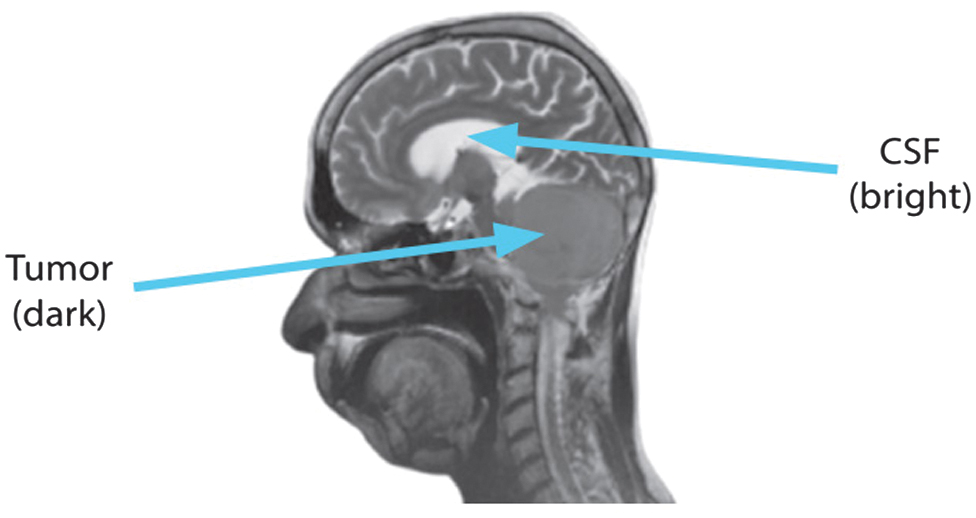

To detect highly vascular lesions, the T1 + C sequence injects contrast material, which amplifies the T1 signal from flowing blood. Everything is as dark as it is in T1, with the exception of the moving blood, which is brilliant. Haemangiomas and lymphangiomas can have their hypervascular lesions identified with its help. The axial view of the T1 + C picture is displayed in Fig. 4.

Fig. 4. Axial view of T1 + C sequence.